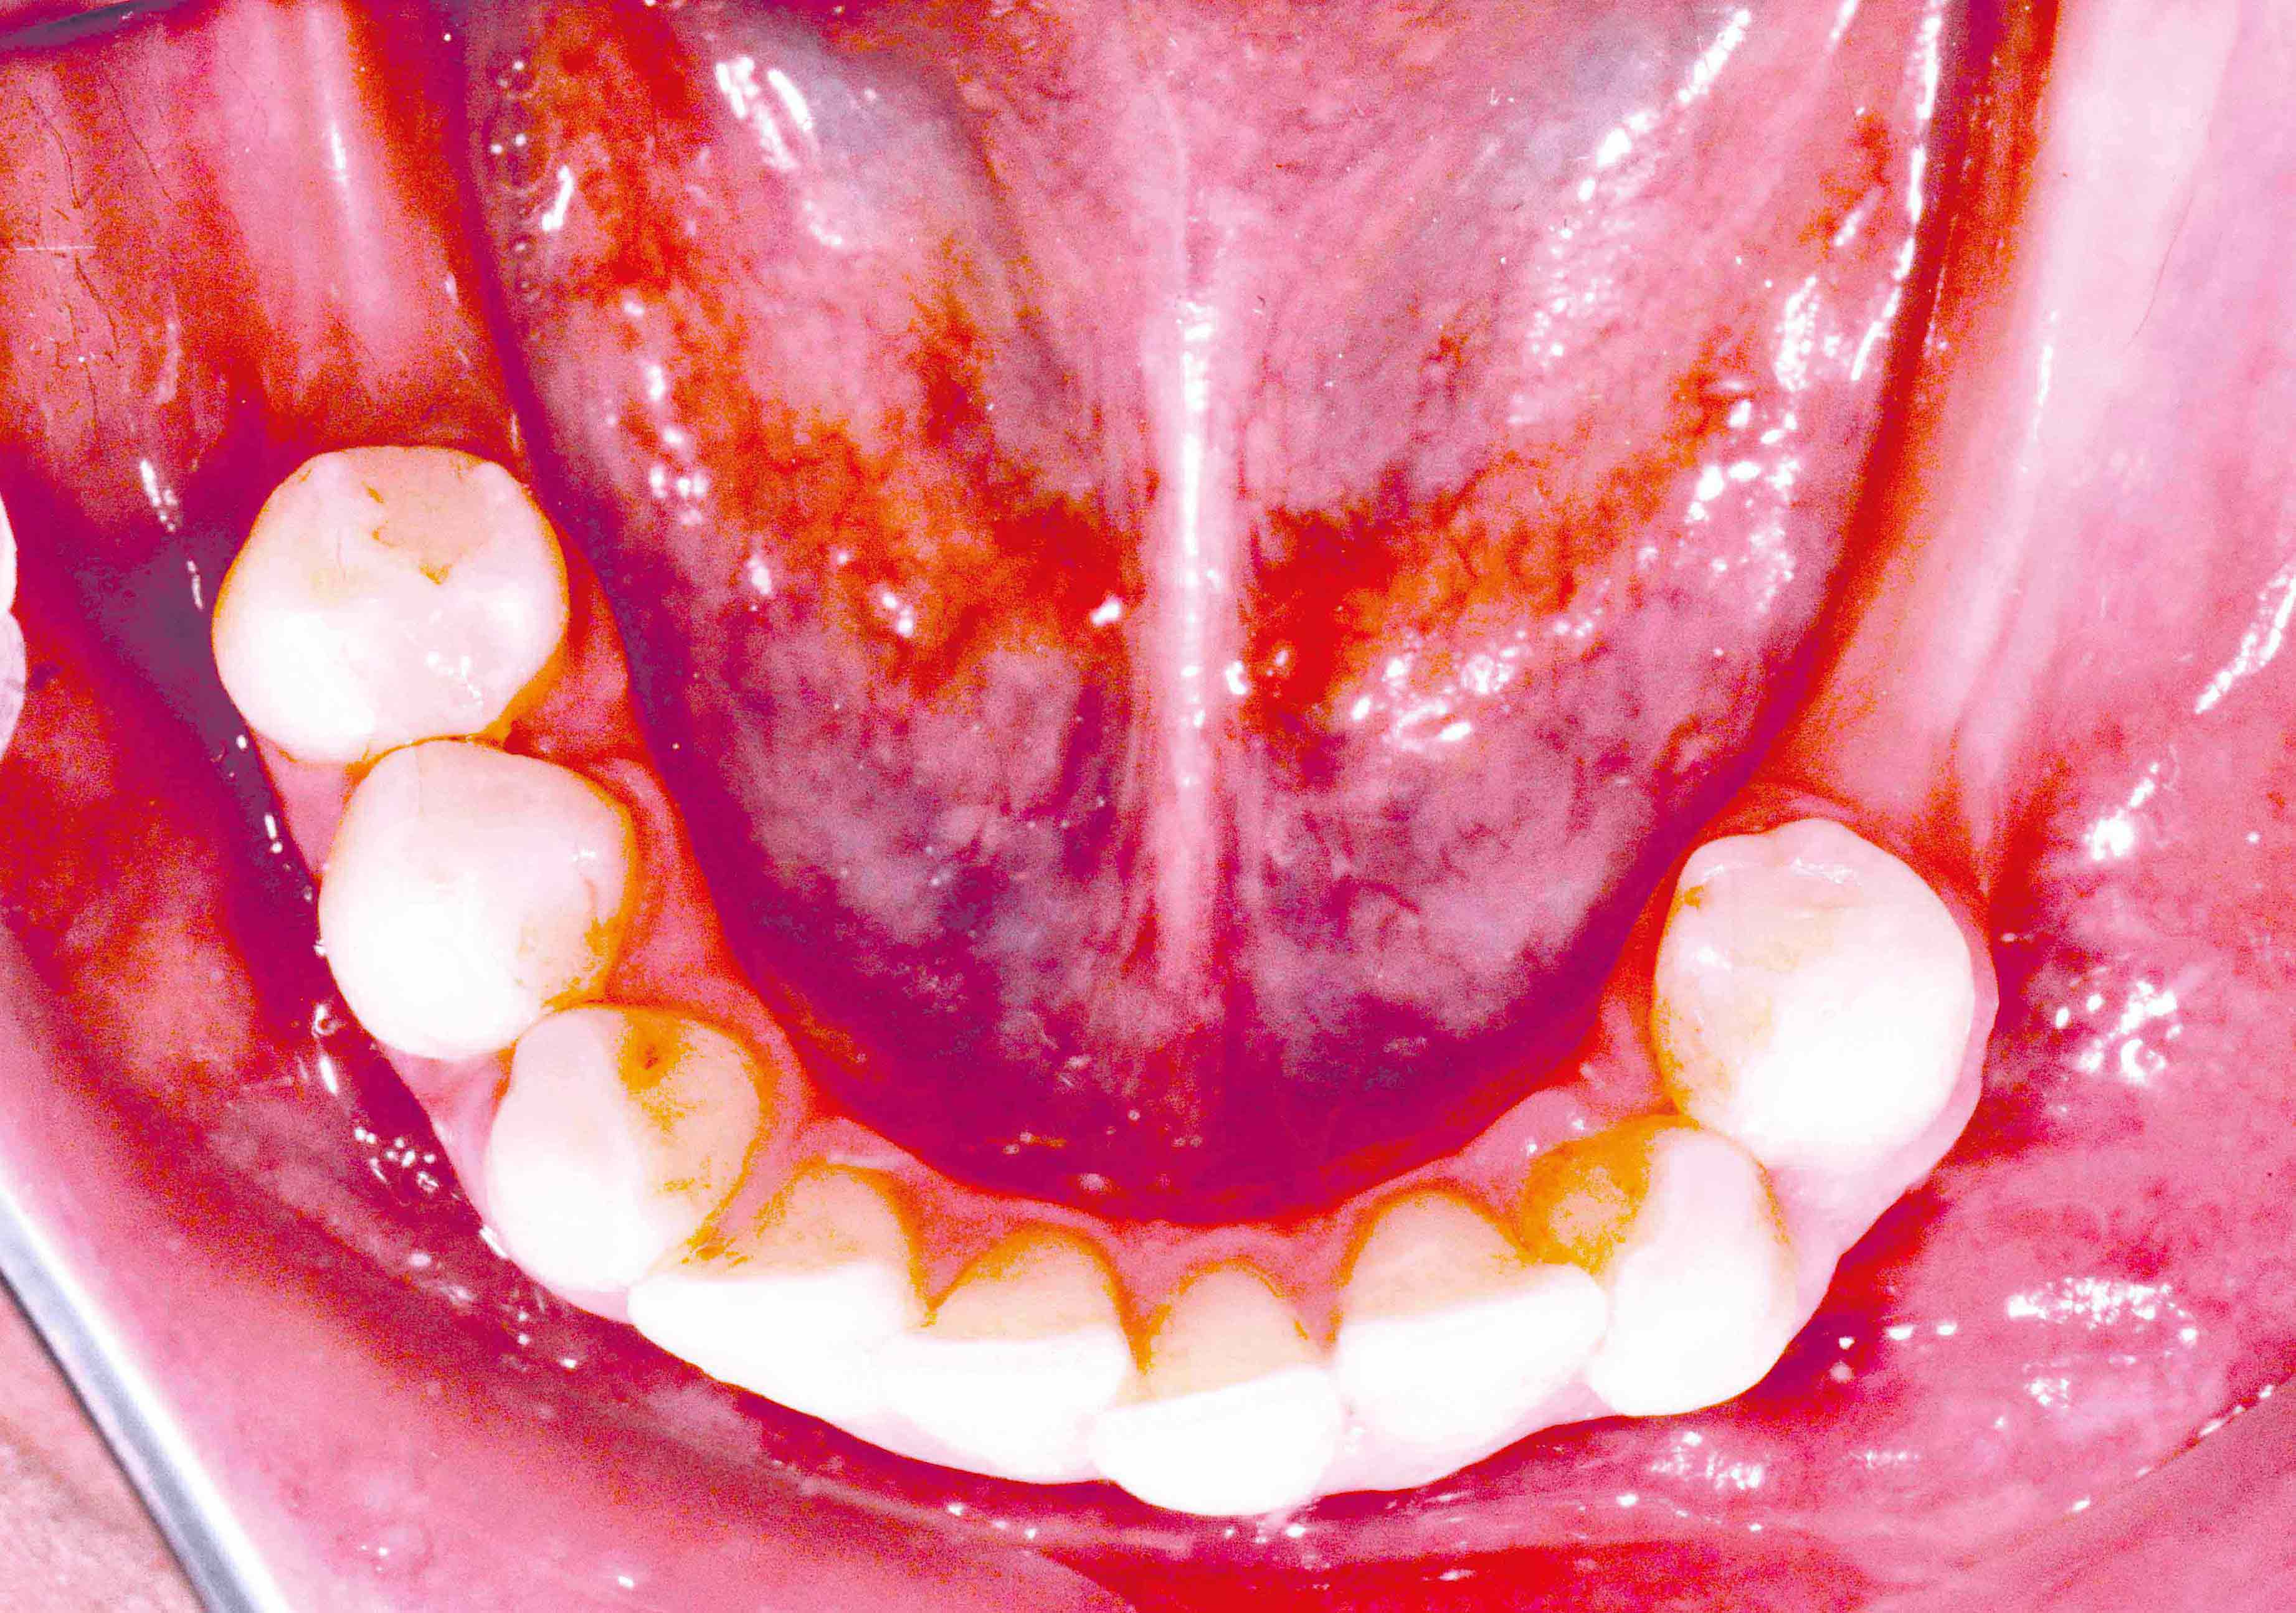

Preoperative situation – Maxillary defect in area 14-16 (loss of implant 16 due to periimplantitis, tooth 14 extracted recently and area 15 already edentulous for a while)